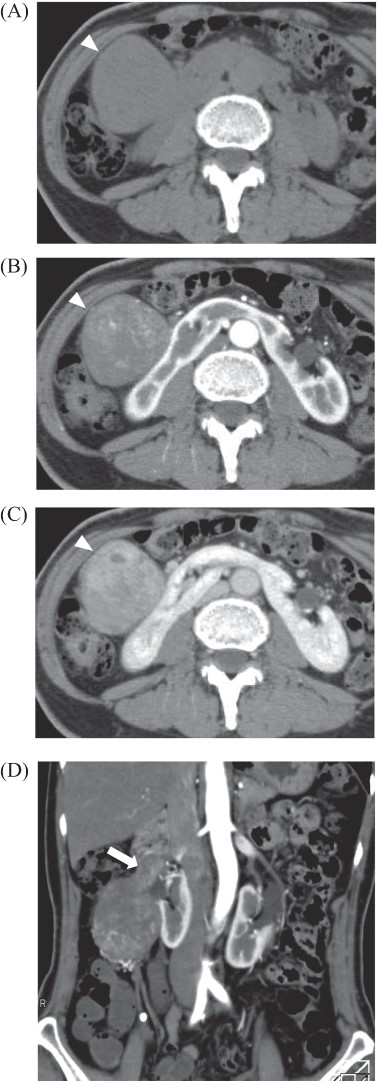

A 69-year-old woman presented to our institution with right abdominal pain. There was nothing special to mention in her family history. Her past medical history included horseshoe kidney, gastric ulcer, and asthma. Physical examination revealed a slight tenderness of the right quadrant abdomen. All laboratory parameters including the tumor markers carcinoembryonic antigen and carbohydrate antigen 19-9 were within normal limits. Abdominal ultrasonography showed a regularly shaped uniform tumor of about 50 mm in diameter that was located in the right retroperitoneum ventral to the right part of the horseshoe kidney. The tumor was hypervascularized (Fig. 1). Computed tomography (CT) showed a tumor of 80 mm in diameter ventral to the right part of the horseshoe kidney and the dorsal side of the descending part of the duodenum. On contrast-enhanced CT, the tumor showed late-phase enhancement. There were no findings of invasion into any organs and right ovarian vein ran through the tumor (Fig. 2). No metastases to organs or swollen lymph nodes were found. Magnetic resonance imaging (MRI) showed a tumor that was isointense with respect to muscle on T1-weighted images and of high-signal intensity on T2-weighted images (Fig. 3). No fatty components were detected in the tumor. Endoscopic ultrasonography showed a regularly shaped and hypoechoic tumor with no connection to the right part of the horseshoe kidney or duodenum (Fig. 4). Our working diagnosis was a retroperitoneal tumor that could be either a malignant lymphoma, leiomyoma or gastrointestinal stromal tumor.

Endoscopic ultrasonography: there was no finding of infiltration to the right kidney and the duodenum.